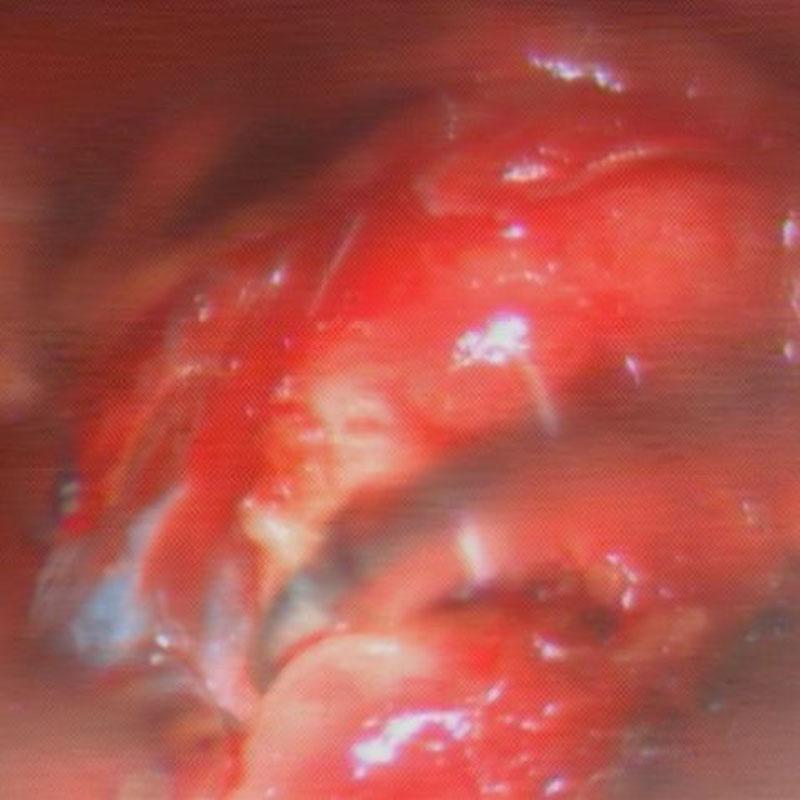

412

'23年5月

20代

小脳血管芽腫

頭蓋内腫瘍摘出術

No.’23_46 手術前1

No.’23_46 手術前2

No.’23_46 摘出 前

No.’23_46  摘出 中

No.’23_46 摘出 後